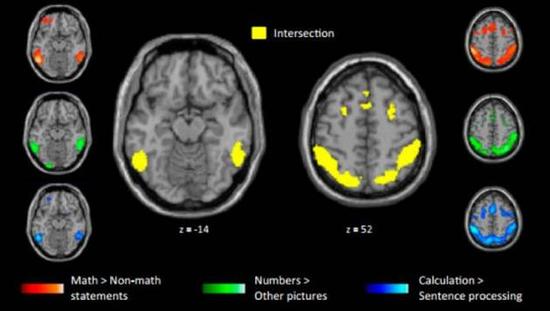

研究人员发现,数学家们只有在听到数学相关的命题时(不管难度如何),大脑中双侧顶内沟区域(bilateral intraparietal sulci, IPS)、双侧颞下回区域(inferior temporal, IT)和前额叶皮层区域(prefrontal cortex, PFC)才会被激活。而这些区域在他们听到非数学命题时甚至会被轻微地抑制。这些大脑区域通常不参与语言和语义处理。当受试者被问及非数学命题时,所有人负责语言和语义处理的脑区域均被激活。

这一研究的共同作者,博士生玛丽·亚马希 (Marie Amalric)说,“我们的研究结果表明,高水平的数学思考所反复利用的大脑区域,正是人脑中与数字和空间认知相关的区域,该区域在多年以前就已形成,并一 直随人类演化到今天。” 同时,他们还发现两组受试者进行简单的数学运算时调用了双侧顶内沟区域(IPS)和颞下回区(IT),与数学家处理高等数学命题时激活的区域重叠。这个结果可以部分支持“核心知识”假说。

处理高等数学命题(红)与进行数字(绿)和计算(蓝)时活跃的区域基本重合。